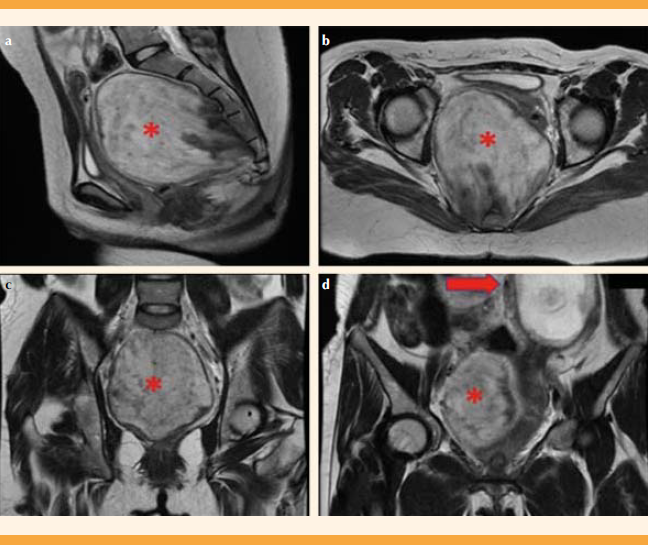

Paciente de 32 años, primigesta, con 16 semanas de embarazo. Acudió a Urgencias debido a un dolor en el hipocondrio derecho, tipo cólico, de intensidad 6 de 10, de 15 días de evolución. En los controles prenatales previos no se habían reportado complicaciones. Las cifras tensionales al ingreso fueron: 120-76 mmHg, frecuencia cardiaca de 75 lpm, frecuencia respiratoria de 18 rpm, temperatura de 36.9 oC. Dolor a la palpación en la parte derecha del hipocondrio, sin signos de irritación peritoneal, con una altura uterina de 15 centímetros, frecuencia cardiaca fetal de 143 lpm. Sospecha diagnóstica: cólico biliar, causa del dolor abdominal. Se decidió hospitalizarla para efectuarle estudios complementarios, y controlar el dolor. El hemograma no reportó leucocitosis ni neutrofilia. Las pruebas de función hepática reportaron que las concentraciones de transaminasas eran normales, lo mismo que de bilirrubinas. La ecografía obstétrica informó adecuado bienestar fetal. La ecografía total del abdomen evidenció colelitiasis y una masa en el fondo de saco de Douglas retroperitoneal, con contornos regulares, hipoecogénica, sólida, de 107 x 96 x 81 milímetros, con captación Doppler central tipo II (Figura 1). La resonancia magnética confirmó la existencia de una masa sólida, de contornos parcialmente definidos, localizada en el espacio presacro, de 100 x 85 x 90 milímetros; hipointensa en T1 e hiperintensa en T2. La masa contenía conductos hipointensos en T2 que se extendían a los forámenes sacros derechos. En las estructuras óseas y vasculares no se identificaron alteraciones (Figura 2). La impresión diagnóstica fue de tumor retroperitoneal, de origen neural. Ante el diagnóstico de tumor de naturaleza desconocida se solicitó el estudio de los marcadores tumorales: CA-125: 39.7 U/mL, antígeno carcinoembrionario: 0.4 ng/mL, antígeno carbohidratado: 19-9 (CA 19-9): 9.35. U/mL. La biopsia percutánea, guiada por tomografía, se informó sin complicaciones (Figura 3). Al segundo día de hospitalización desapareció el cólico biliar, razón para otorgarle el alta hospitalaria.

Figura 2 Resonancia magnética del ganglioneuroma. La lesión en el espacio presacro se aprecia con contornos parcialmente definidos, de 100 x 85 x 90 milímetros, en fase T2 hiperintensa, con conductos hipointensos que se extienden a los forámenes sacros derechos; a. corte sagital; b. corte axial; c. corte coronal; d. corte coronal de relación ganglioneuroma (*) con útero grávido (flecha).